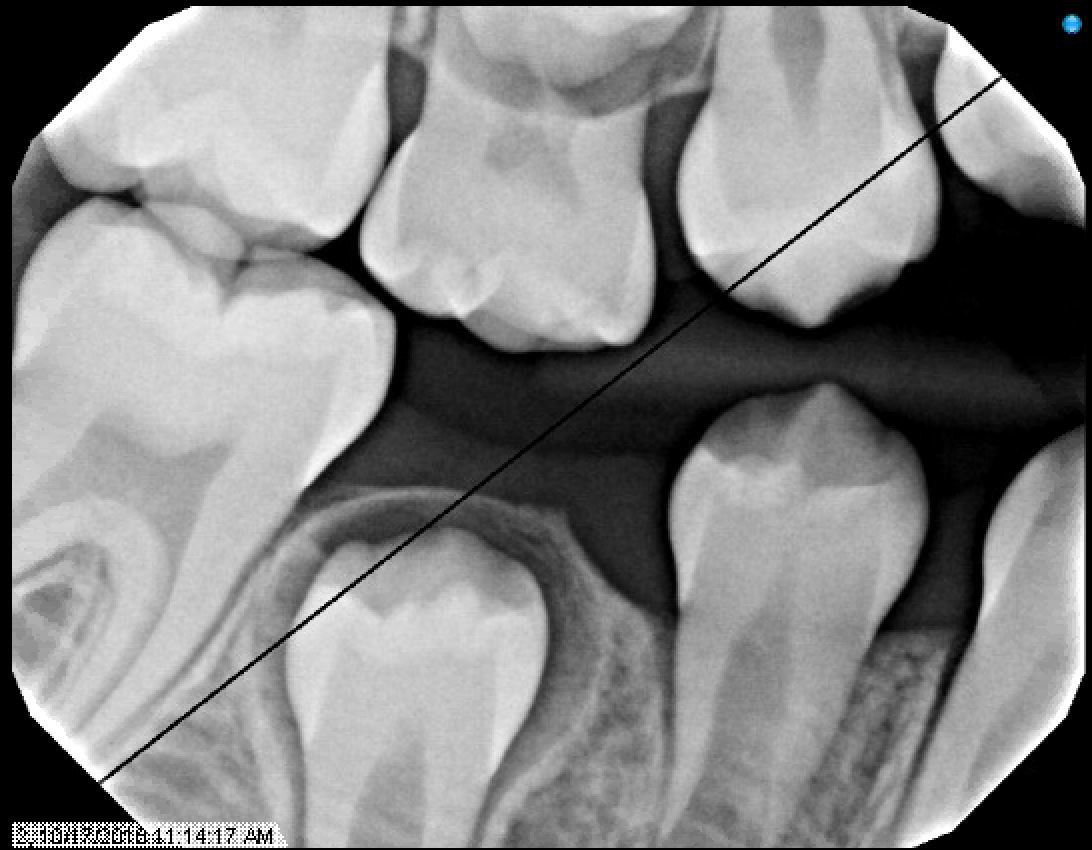

Radiographs from 10/17/18 - School Based Dental Program @ PS188

Since this patient was already seen a year ago in NYUCD. This visit was considered a recall visit.

Due to the clinical carious lesions present - 2 BW radiographs were recommended to observe any interproximal carious lesions (also to update the treatment plan that was never fulfilled) and PA#8 to observe the location of mesiodens and any update in eruption of #8 or the mesiodens.

Radiographic Interpretation revealed: Carious lesions in #3-O, #A-O, #14-O, #19-OB, #K-MOD, root tip present in tooth #L, #30-O, Mesiodens present ( disrupting the proper eruption of tooth #8) ***

Figures 12, 13, & 14: Recall bitewing radiographs 10/17/18 @PS188 School Based Dental Program